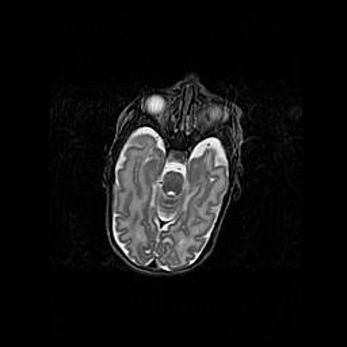

Наружная гидроцефалия с возможной атрофией височных областей.

Возраст: 28 дней

Вес: 3670 г

Пол: мужской

Окружность головы: 38 см

Срок гестации: 40 недель

Гидроцефалия головного мозга у новорожденных – это заболевание, которое характеризуется скоплением избыточного количества спинномозговой жидкости в желудочковой системе головного мозга в результате затруднения её перемещения от места выработки к месту поглощения в кровеносную систему или вследствие нарушения абсорбции. При открытой наружной форме гидроцефалии у новорожденных расширяются и переполняются субарахноидные пространства.

При нормотензивных  формах,  которые,  как  правило,  являются  следствием  перенесенных ишемических  повреждений  паренхимы  мозга,  возможно  сочетание микроцефалии  с нормотензивной гидроцефалией. В основе данных изменений лежит атрофия больших полушарий с преимущественной  локализацией  в  лобно-височных  областях.